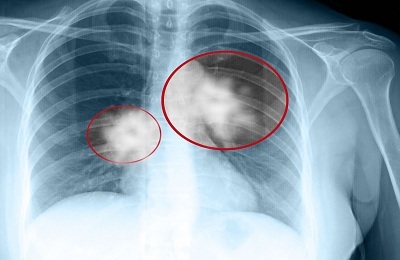

Рентгенографический снимок. Это метод один из самых распространенных при ранней диагностики рака легкого. Хотелось бы отметить, что на снимке можно заметить не четкость, размытость и неоднородность контуров новообразования. Для того чтобы определить данным способом наличие раковой опухоли и поставить правильный диагноз, с момента появления данного заболевания должно пройти около 126 календарных дней.- Магниторезонансная томография. Выявление злокачественной опухоли в тканях легких на ранних стадиях таким способом дает наиболее точную информацию о состоянии плевральной жидкости, состоянии сосудов легочных тканей и степени заражения данным процессом смежных органов.

- на рентгенографическом снимке заметен неоднородный плотный сегмент,

- появление затененных участков, видимых на рентгеновском снимке, в виде овальной формы с выявленными неровными краями,

- если имеется явное поражение лимфоузлов, то на снимке будет прослеживаться дорожка, отходящая от зоны поражения к основанию легкого.

Базой для констатации наличия новообразования в легких является рентгеновский снимок. Увидеть аномальный участок в легком — задача простая, установить старт того же процесса на первых этапах, довольно сложно.

Причина состоит в том, что при первом визите к специалисту пациент описывает симптоматическую картину, присущую многим заболеваниям дыхательной системы. Рентген может четко определить наличие патологического процесса, что и послужит поводом для последующего обследования.

Мнение о том, что опухоль на снимке имеет округлую форму не совсем верно. Рак лёгких на ранних стадиях (опухоль диаметром до 2 см.) чаще выглядит как звездчатый рубец с нечеткими размытыми контурами. Только по мере роста картина опухоли приобретает округлую или овальную форму.

Также обращают внимание на рентгенологические проявления стеноза (сужения) бронхов, состояние окружающих органов, тканей, лимфатических узлов. Рак лёгких на флюорограмме ничем не отличается от такового на рентгенограмме.